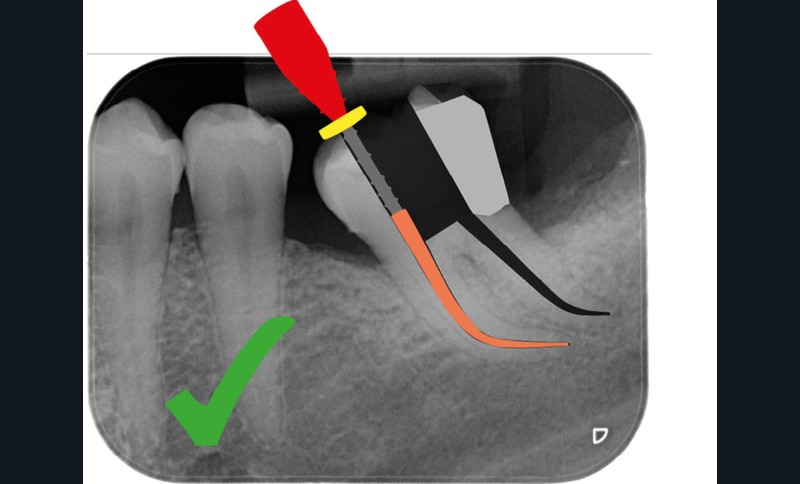

Une cavité d’accès trop large optimiserait le pronostic endodontique mais compromettrait le pronostic biomécanique. C’est le cas de la cavité d’accès traditionnelle, qui a longtemps été « au service » du praticien réalisant le traitement canalaire (dentist-centered dentistry ou dentisterie centrée sur le praticien). Les étapes d’instrumentation, d’irrigation et d’obturation étaient ainsi facilitées grâce à des accès visuel et instrumental exagérés, aux dépens de structures dentaires saines (fig. 4).